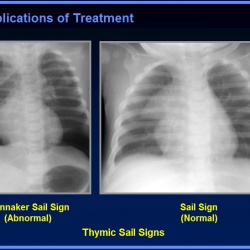

5. Пневмомедиастинум.

6. Важный признак пневмомедиастинума - подъем вилочковой железы, симптом косого паруса (спинакера - Spinaker sign).

7. Собственно, сам косой парус - спинакер.

8. Бывает и такой подъем и разворот тимуса.

2. на картинке номер 8. это такой вариант нормы или тоже пневмомедиастинум?

Номер 8 - это пневмомедиастинум. Не могу сказать, есть ли в картинке неомер 6 пневматоцеле (это иллюстрация, а не наблюдение). Те пневматораксы, которые я видел, были более выражены.